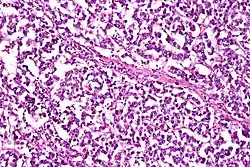

Las células del disgerminoma se agrupan en cordones o sábanas,[2] tienen un citoplasma claro con un núcleo central, liso, con cromatina granular y nucléolos evidentes.[1] El estroma se compone de bandas fibrosas[2] que contienen linfocitos y, en menor cantidad, histiocitos, sincitiotrofoblasto y granulomas.[7] Las células del sincitiotrofoblasto producen gonadotropina coriónica humana (hCG).[6] En cuanto a su inmunohistoquímica, suelen ser positivos para SALL4 y OCT3/4, pero, a diferencia de otros carcinomas de células claras, son negativos para EMA y casi siempre para queratinas.[7]